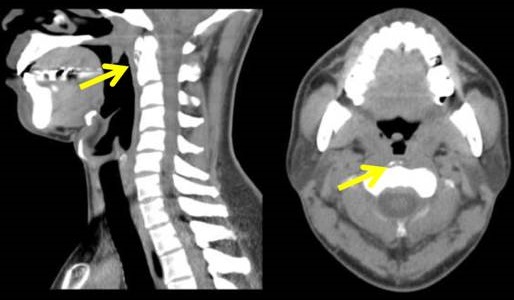

石灰沈着性頸長筋腱炎(Calcific Tendinitis of the Longus Colli Muscle)は20~50歳に多く、頸長筋腱の虚血・過使用によって発症する炎症で、石灰沈着を伴います。

石灰沈着性頸長筋腱炎の症状は、

- 急性の頸部痛;むしろ喉(のど)の奥に生じる痛みで、甲状腺とは明らかに位置が違います

- 嚥下痛

血液検査では炎症所見を認めます。咽後膿瘍(後咽頭膿瘍)や化膿性脊椎炎、甲状軟骨骨折、甲状舌骨靭帯症候群との鑑別が重要[J Yeungnam Med Sci. 2023 Nov;40(Suppl):S129-S133.]。咽後膿瘍(後咽頭膿瘍)は甲状腺に到達すると急性化膿性甲状腺炎と甲状腺膿瘍を引きおこすので要注意。

頸椎単純X線・CTで第1-2頸椎前面の頸長筋腱付着部に石灰化。MRI では椎前間隙-咽頭後隙の腫脹・浮腫・液体貯留。